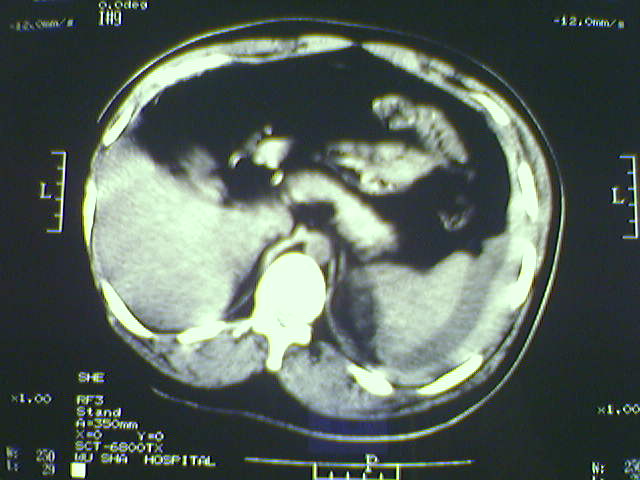

以下是引用zjzjr在2008-6-3 21:01:00的发言:[br]腹腔积液+邻近软组织肿厚.考虑感染性病变可能性大.